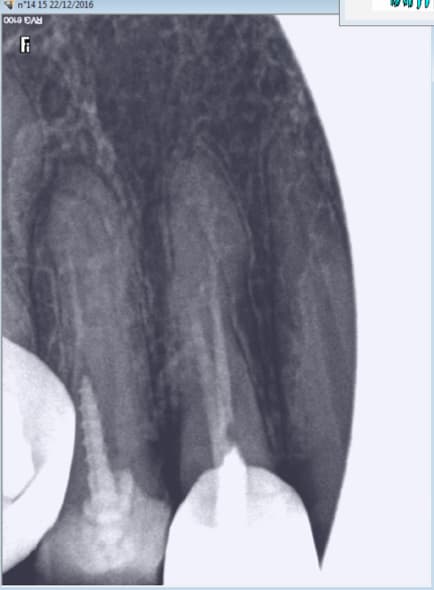

C'est rien ca, je te présente des travaux conforme aux tarifs de la grande sécurité sociale française d'un praticien qui gagne bien sa vie

Nb : le oatient venait car le bridge secteur 3 se casse la gueule : IC de 0.1 mm (sans blague), et couronne pas aux limites (qui sont de toute façon pas taillées)